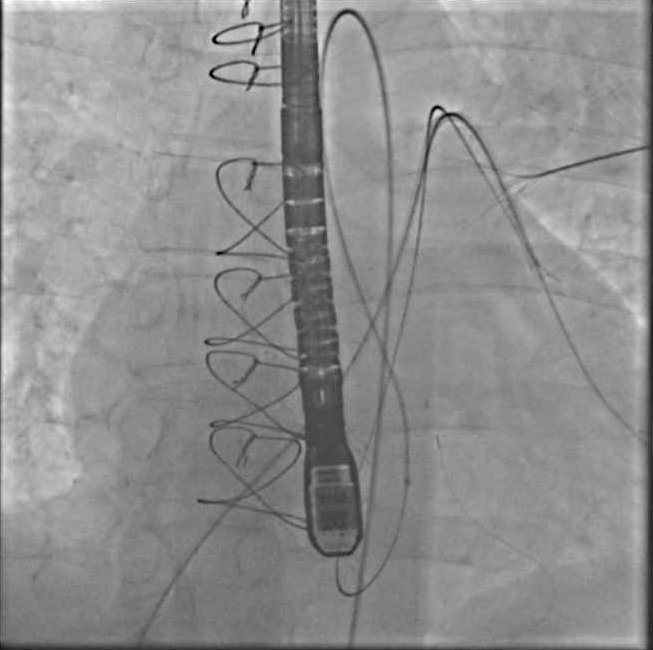

9- We changed strategies and deployed the device via the arterial side. Delivery system (Amplatzer) was not be long enough 10Fr 80cm via Ao side, hence, we used a 90 cm 8Fr shuttle sheath. Required acrobatics to get device into the sheath.

10- Device deployed successfully without interacting with valvular structures. Qp:Qs dropped from 2.3 to 1.2. SBP acutely increased 40-50 points. Note: Usually takes time for a good seal to form.